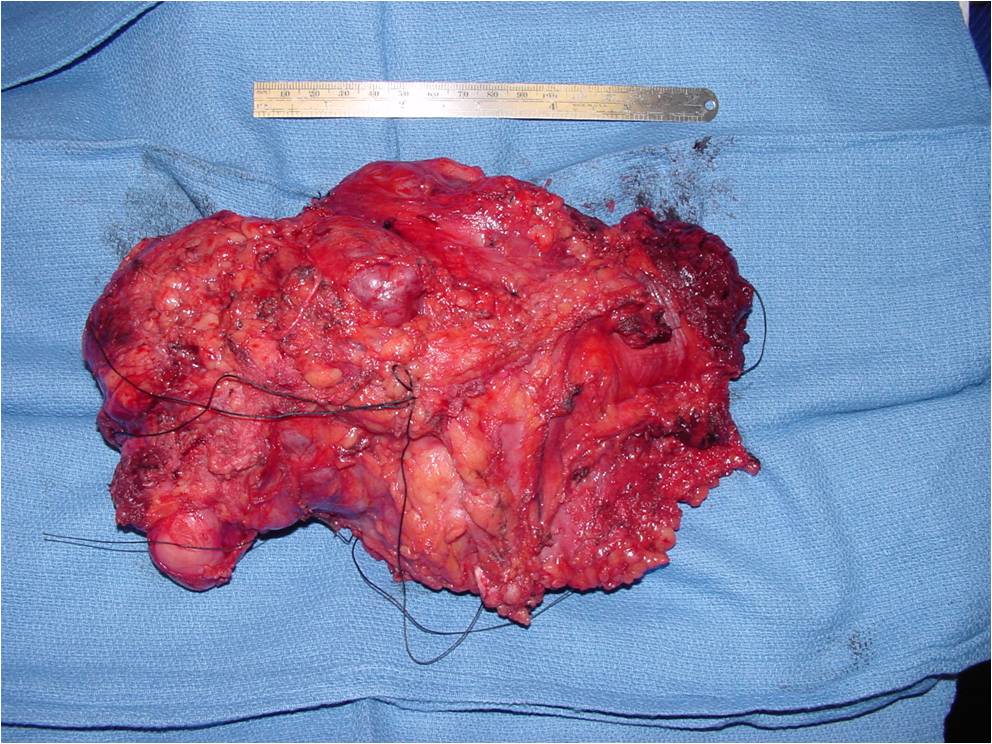

Gross Pathology

- Gross appearance is variable

- Ranging from soft to firm

- Gray to pink

- Occasionally have a faintly lobulated pattern

- Grossly obvious cartilage is rarely visualized